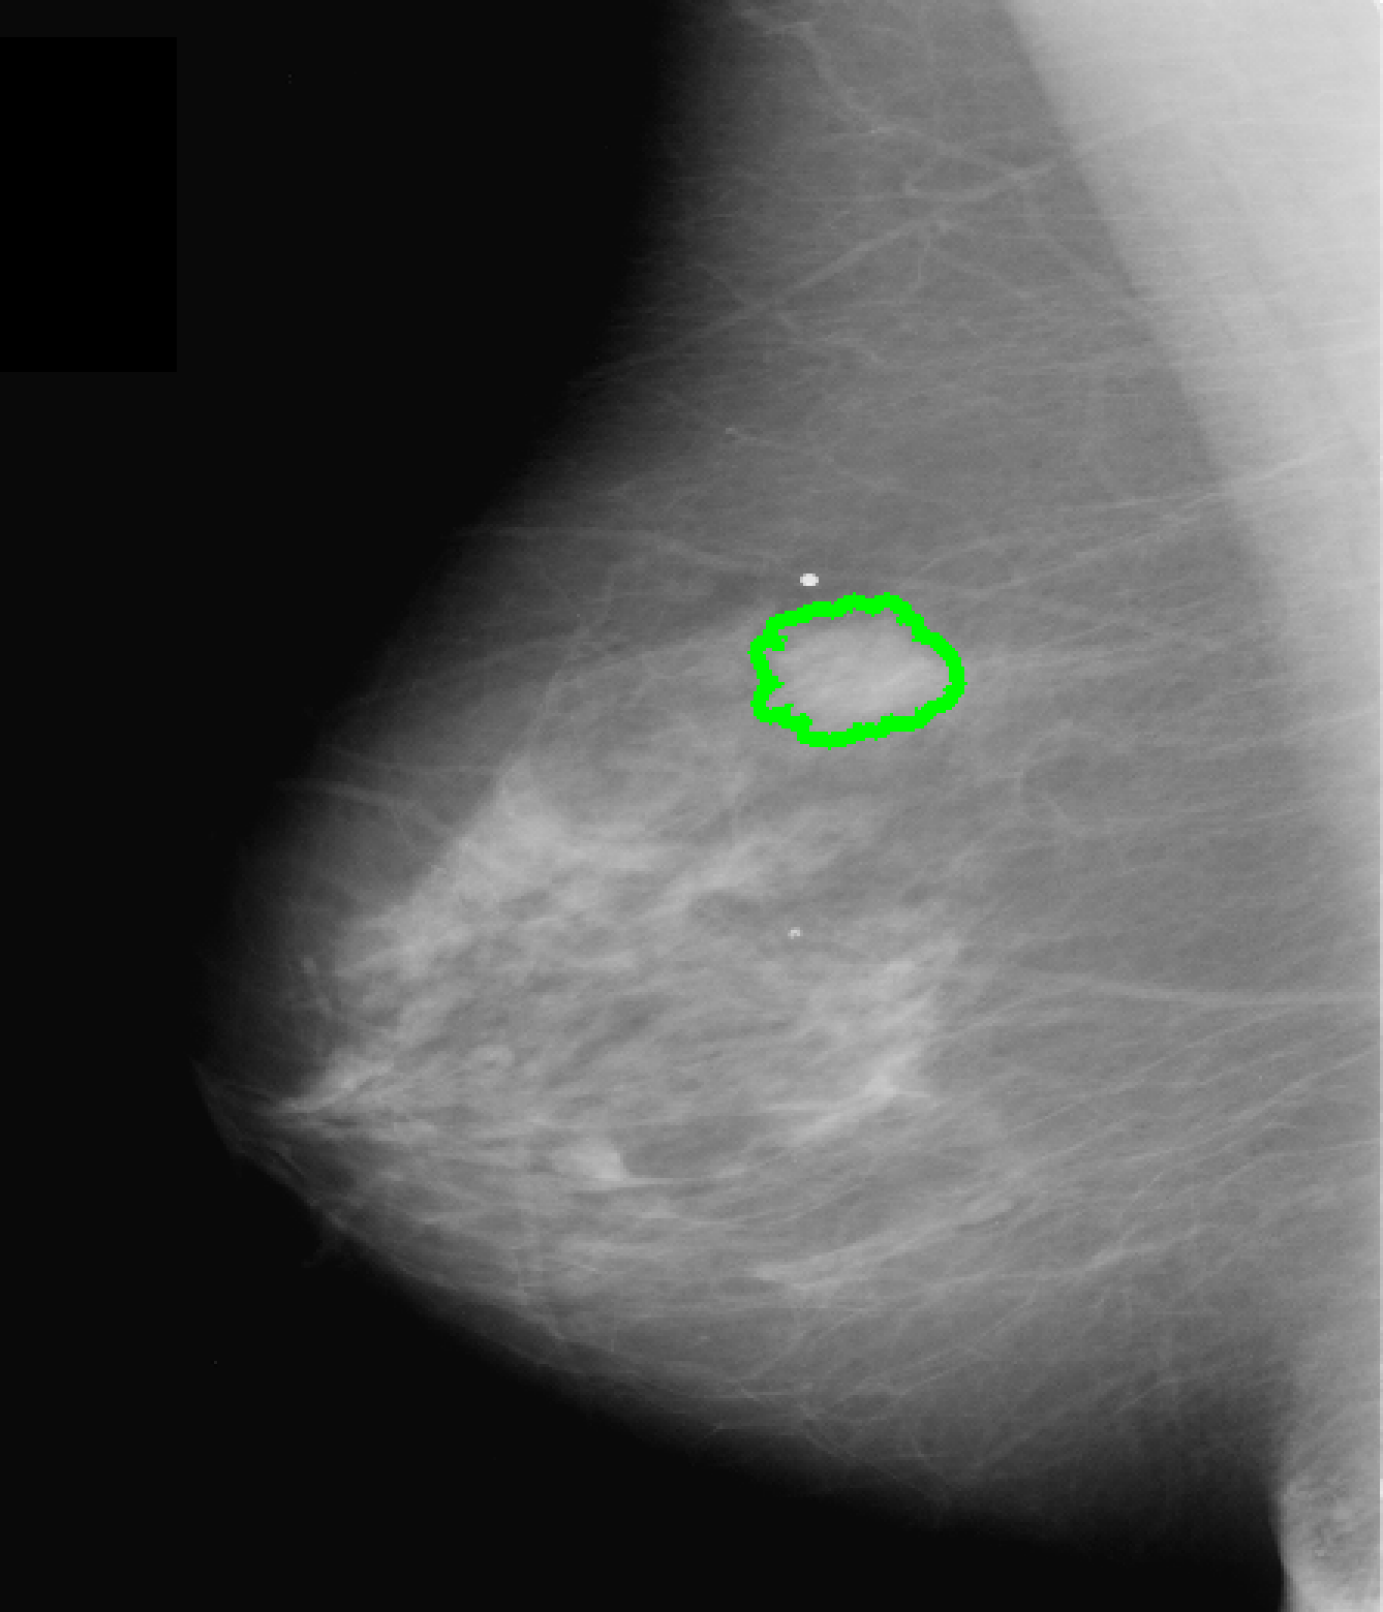

Our goal is to estimate a faithful and informative saliency map between a medical image and its classification score: given an image, we search for and visually attribute the specific pixel-set that contributes towards a confident classification for a fixed class (see Fig. 1). Following [4, 2] we formulate the general problem as finding the smallest deletion region (SDR) of a class , i.e. the pixel-set whose marginalization w.r.t. the classifier lowers the classification score for .

Qualitatively, as depicted in Fig. 3 (b), our salient regions appear at the circumference of masses which is reasonable w.r.t. the fact that this is the discriminative region for the presence of masses. This is in line with [16], which reports on injection of poorly circumscribed, malignant looking masses while transforming healthy cases into pathological ones using a GAN variant. In addition, our method yields more accurate visualizations than CAM and SAL (Fig. 3 first row), i.e. it has a smaller, more precise and more informative feature attribution than these standard visualization methods (Fig. 3 (b)-(d)).